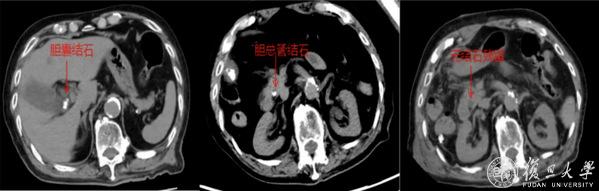

近日,100岁的陈爷爷突然右上腹剧痛、高烧不退,急诊确诊为:胆囊结石伴急性胆囊炎、胆总管结石伴急性胆管炎。老人免疫力差,感染像野火一样蔓延,再不动手术就可能休克甚至丧命,但传统开腹手术创伤大,术后并发症风险极高,对百岁老人来说更是风险堪比“走钢丝”,如何选择手术方式成为治疗关键。

经多学科团队综合评估后,复旦大学附属浦东医院肝胆外科主任王晓亮、主任医师李春生团队决定采用腹腔镜联合经胆囊管胆总管取石术(TC-CBDE)帮助老人渡过难关。

手术台上,医生先切除了穿孔坏疽的胆囊,再像“穿针引线”一样,通过胆囊管这个“天然隧道”,把胆总管里的结石一颗颗取出来。全程90分钟,未出现胆道损伤、出血等并发症。术后重症医学科蔡金芳主任团队监护治疗,为老人安全保驾护航。术后第二天转入普通病房,术后7日便康复出院。

这种技术有三大好处。一是不切开胆总管,传统手术切开胆总管后得插管引流,住院时间长且存在胆漏、胆管狭窄等风险,而现在通过胆囊管取石,能避免胆总管损伤,降低术后并发症。二是手术时间短、创伤小,腹腔镜微创切口小,对心肺功能较差的老人更安全;三是恢复快,术后无需长期带管,老人能早吃饭早活动,恢复速度远超传统手术。

“高龄不是手术禁区,关键看技术能不能‘量体裁衣’。”团队介绍,此次手术靠多学科联手,才让百岁老人闯过难关。如今,这种微创技术为更多高龄胆道疾病患者点亮了生命希望。